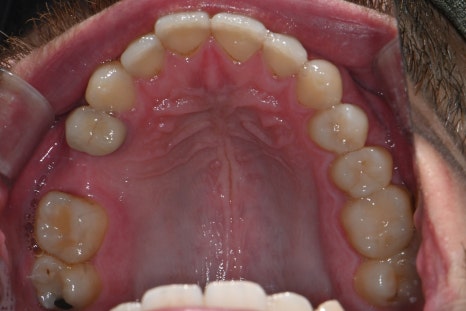

내원 당시 촬영한 위 아래 구강 내 사진입니다.

오른쪽 위 두번째 작은어금니의 상실로 임플란트 치료가 필요한 상태였습니다.